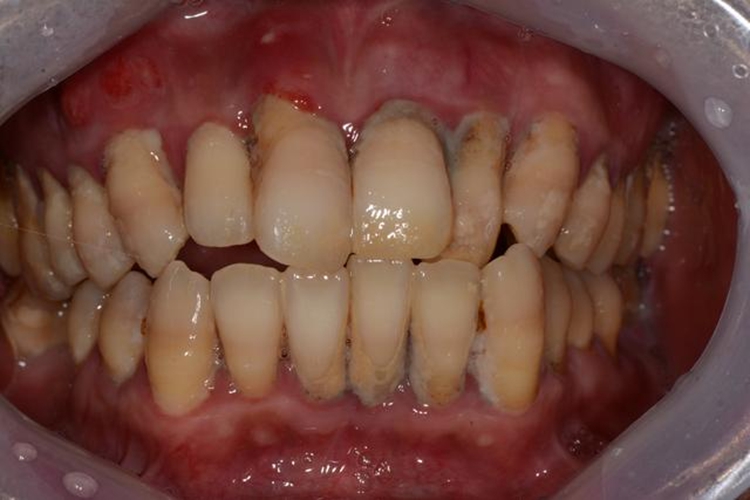

牙结石:可有牙齿发黄、口臭、牙龈出血等症状表现。

龋齿:牙齿病变部位多由半透明的黄色变为浅褐色或黑褐色,随病情进展,还可伴有牙龈出血、牙痛等症状。

牙周炎:患者可有牙龈红肿、齿间出血、牙齿松动等症状表现。

龋齿:进食后不好好刷牙,食物残渣堆积容易滋生细菌,细菌的代谢产物可以破坏牙齿和牙周组织,酸能使牙齿的无机物脱矿、有机物溶解,形成窝洞,成为龋齿。同时食物本身含有的糖类、碳水化合物等成分,在细菌的代谢作用下,产生酸性物质,进而也会破坏牙齿,导致龋齿。

牙结石:牙结石是由于食物残渣、唾液中的矿物质,在菌斑的酸蚀作用下堆积、附着在牙齿上的一种衍生物,不易脱落,其形成原因与唾液成分、饮食习惯和口腔卫生习惯等因素有关。

牙周炎:牙周炎是多因素疾病,如牙石、食物嵌塞、不良修复体、牙排列拥挤、解剖形态的异常等,均可成为牙周炎的局部促进因素。另外营养代谢障碍、内分泌紊乱、牙龈炎等疾病具有可能导致牙周炎的出现。